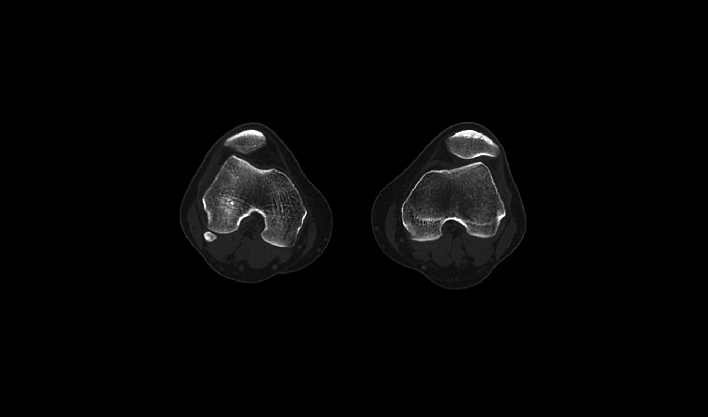

闪速扫描 百万级像素细腻图像

40mm轴向覆盖 满足各部位大范围扫描

3秒完成全肺扫描 减少呼吸伪影